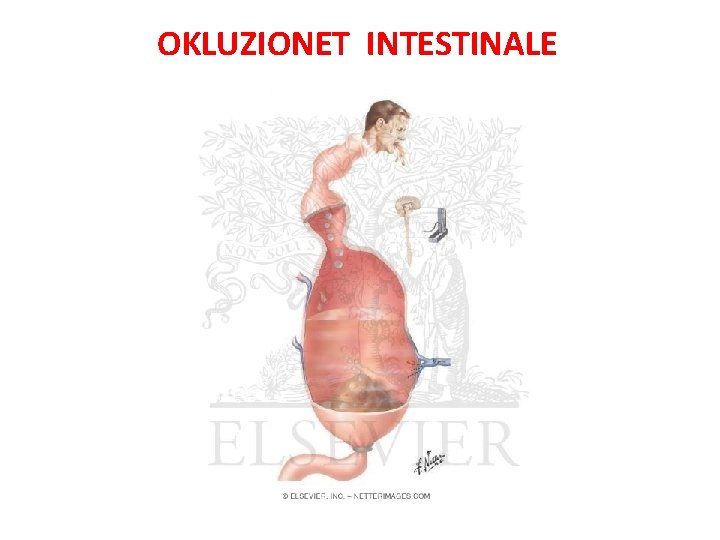

OKLUZIONET INTESTINALE

• Okluzioni Intesitnal ( Ileusi) OI eshte mos eliminimi i transitit te materialeve fekale , tretesirave digjestive e te gazrave nga pengesa te ndryshme mekanike ose parelitike.